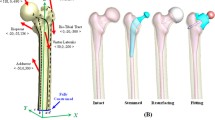

Inspired by the full metal jacket principle of bullets, a double-layer hip stem with a titanium shell and a bone-marrow-like core was developed. A similar approach was realised in the form of the Epoch® prosthesis (Zimmer Inc, Warsaw, USA), however in different material layer order [19]. In our study, every stem was designed in three different phenotypes: full-body titanium (FB), double layer with a 1.32-mm big shell (BS), and double layer with a 0.66-mm small shell (SS). In FEA, the double layer concept was realised by assigning bone-marrow-like elastic modulus to the stem’s core (Fig. 1).

Virtually generated finite element models of the Fitmore®-prosthesis. The figure shows the modelling of the hollow stems with thinning shells. A Full-bodied original stem, B double-layer stem with a 1.32-mm big shell, and double-layer stem with a 0.66-mm small shell (C). Graphics were taken from Ansys®